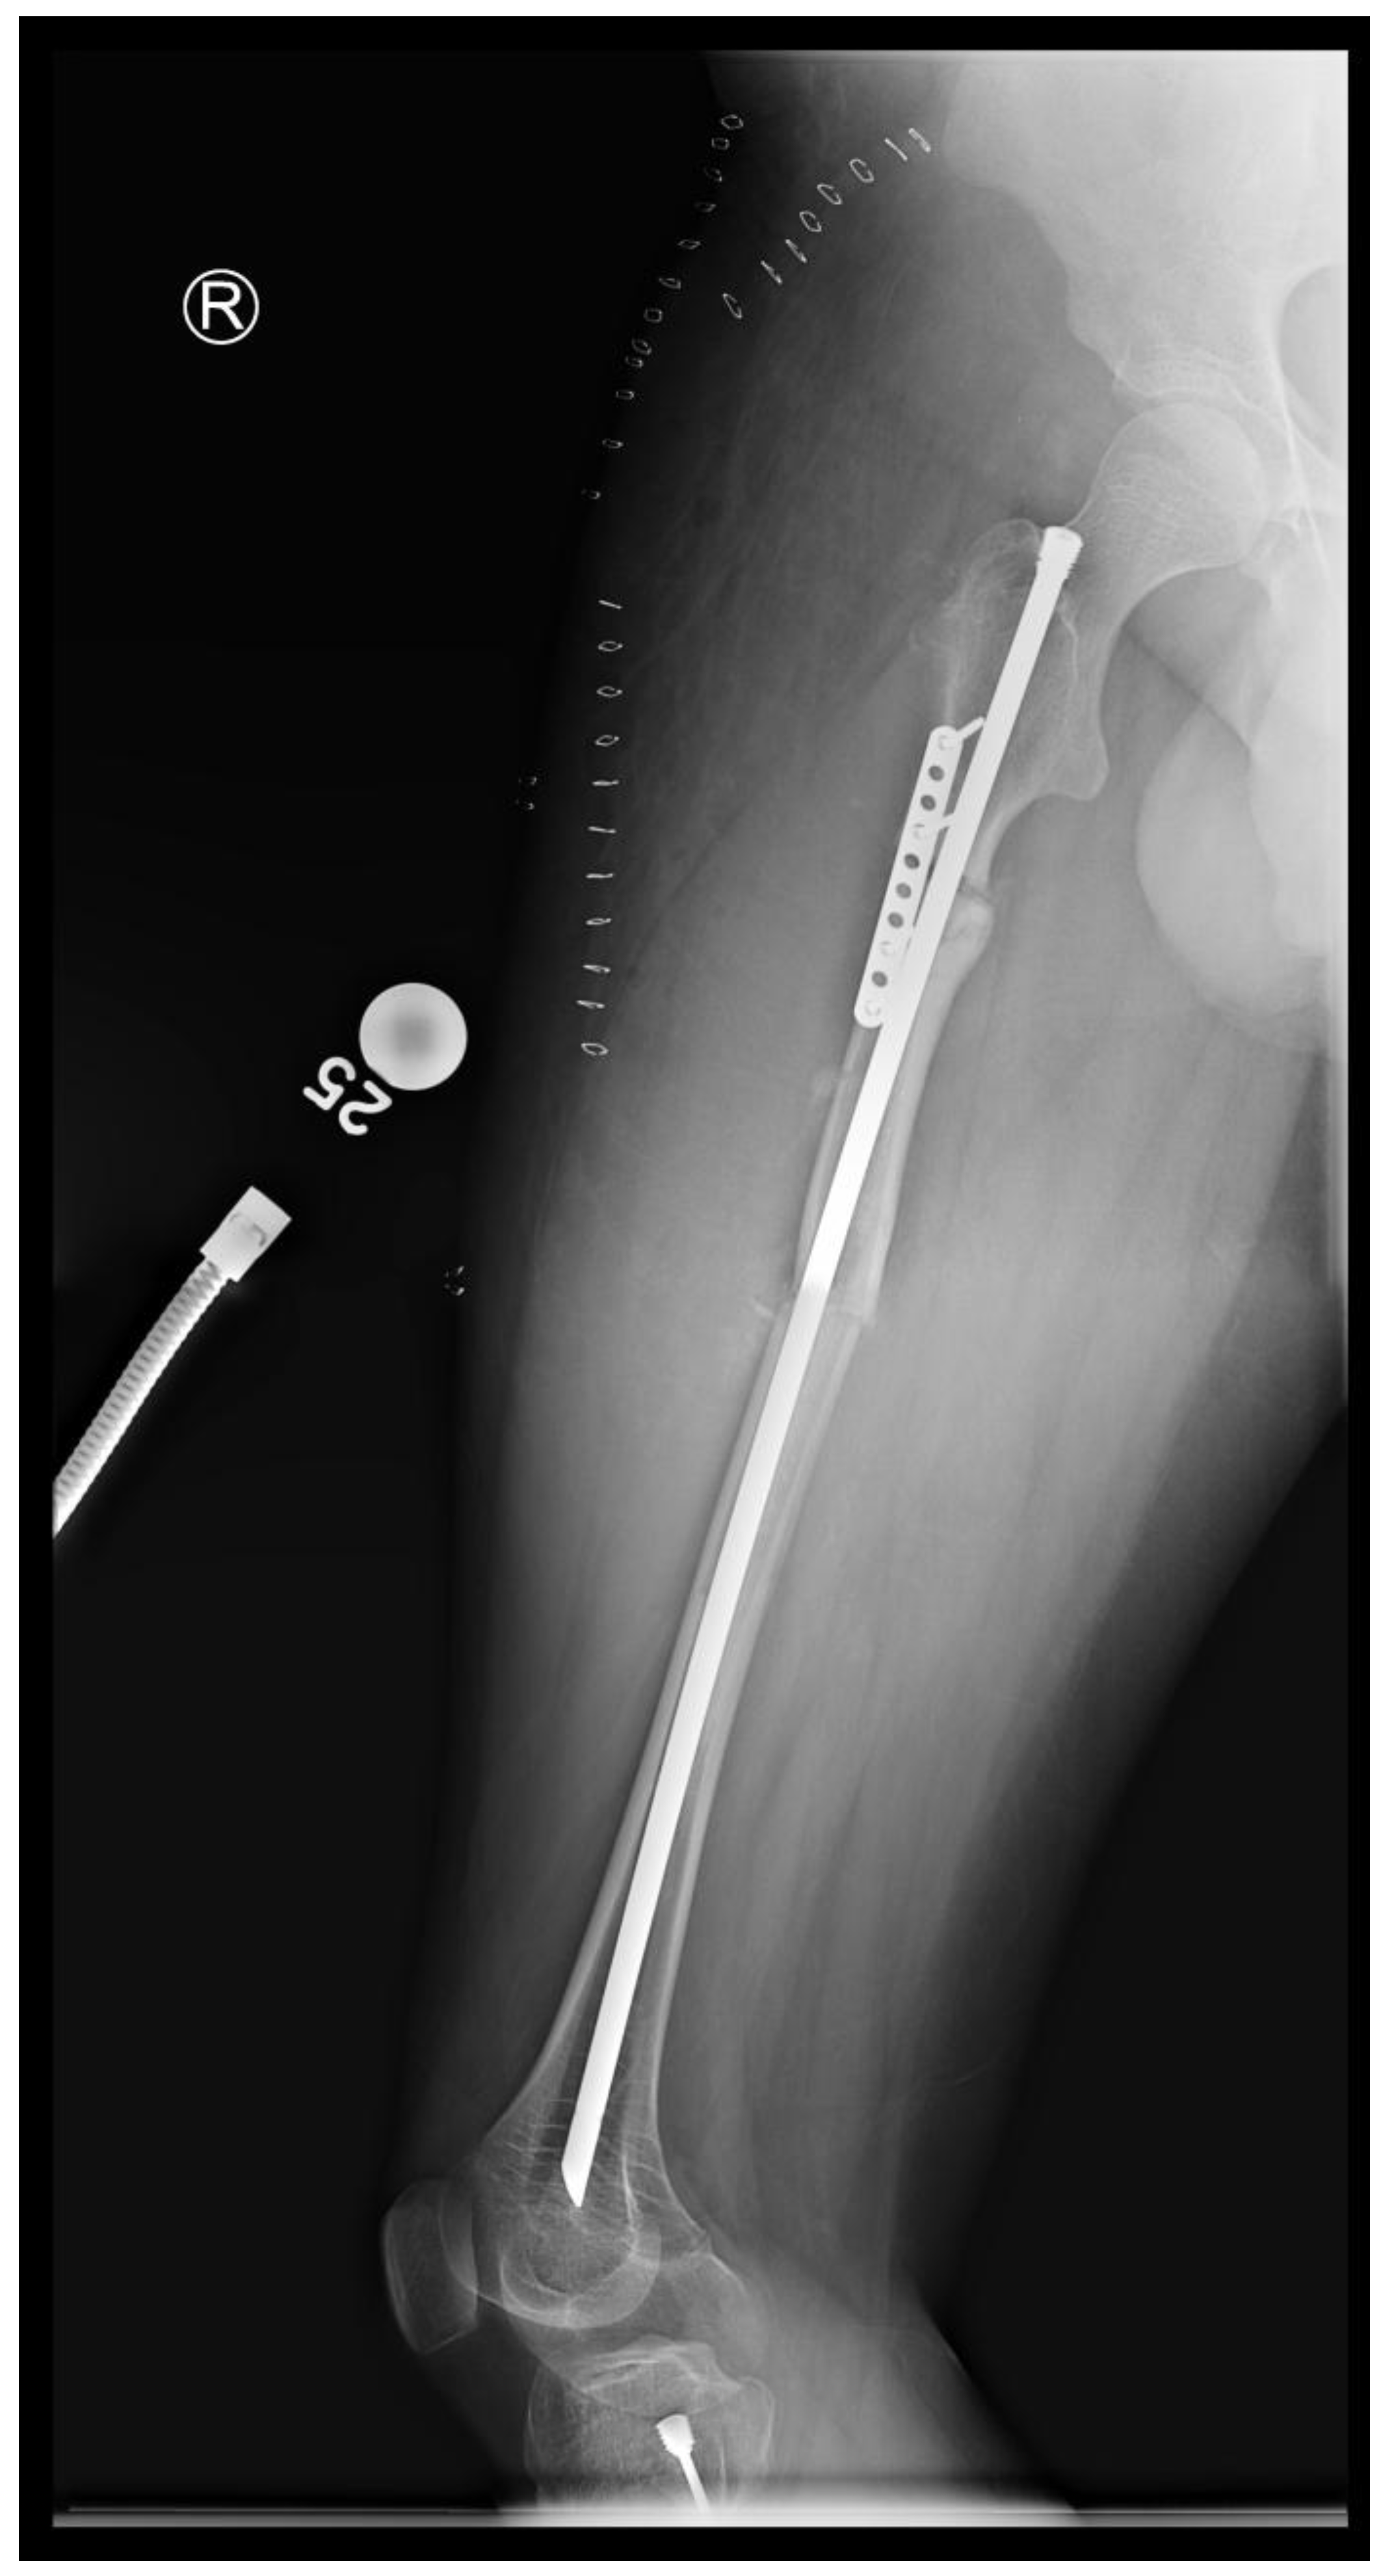

Figure 12. Intraoperative X-rays showing the first CORA and alignment with the continuation of the reaming.

Figure 13. Intraoperative X-rays showing the second CORA and realignment with the continuation of the reaming.

In the third case, a 16-year-old skeletally mature patient with OI was scheduled to undergo revision from FD rod to SLIM nail after presenting with pain due to stress fractures and wild deformity in his proximal right femur (Figure 11). The FD rod was removed, and then, using a piriformis entry point, access to the femur and proximal reaming was done. There were two CORAs; the first CORA was identified in the subtrochanteric region, and a percutaneous osteotomy technique was done to realign the bone, and then reaming was continued (Figure 12). The second CORA was identified, and another percutaneous osteotomy was done, and the bone was cracked with a closed osteoclasis technique, and then reaming was continued in the distal segment (Figure 13). The SLIM nail was then inserted and had an excellent fit. The subtrochanteric region was under high stress, so a 2.7 Smith and Nephew EVOS plate to further stabilize the segment and control the rotation. Two screws were placed above and below (Figure 14). In this case, the indication for the use of the SLIM nail was the need to revise the existing telescoping FD rod in a skeletally mature patient to a solid nail. As the intramedullary canal was too small to accommodate a larger solid nail, a SLIM nail was used instead. The use of a plate as an adjunct to an intramedullary nail is also shown.